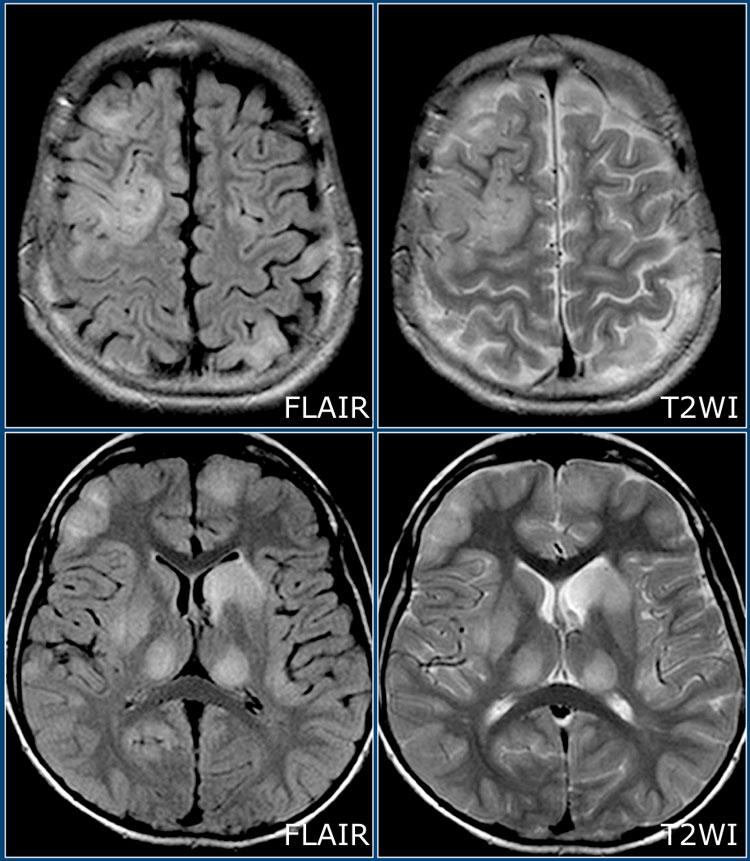

Hình ảnh MRI trong bệnh xơ cứng rải rác (MS)

Bảng tóm tắt các đặc điểm MRI điển hình trong bệnh MS.

Đây là hình ảnh FLAIR và T2W cắt ngang của một bệnh nhân trẻ mắc ADEM – lưu ý tổn thương lan rộng ở chất xám vỏ não và chất xám sâu, bao gồm đồi thị.

Đây là một trường hợp ADEM khác.

Lưu ý tổn thương ở hạch nền và cuống tiểu não giữa.

Lưu ý sự tương đồng với hai trường hợp còn lại.